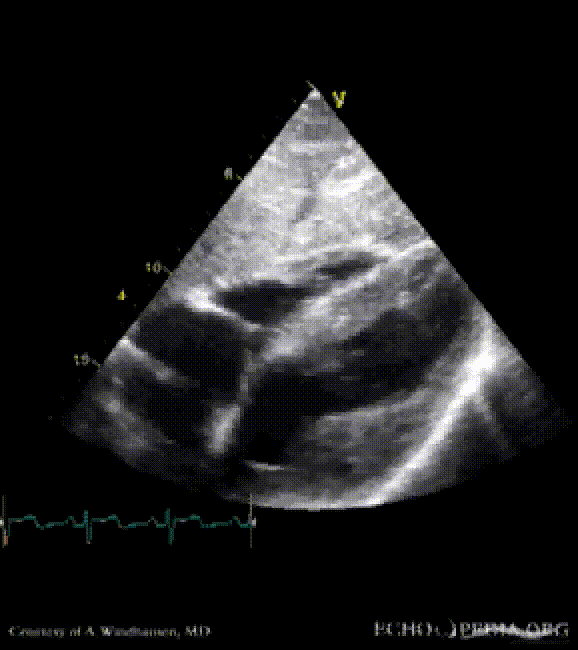

Severe Hypertrophic Cardiomyopathy (HCM)

Case description: Severe Hypertrophic Cardiomyopathy (HCM)

Courtesy of: A. Windhausen, AMC, The Netherlands